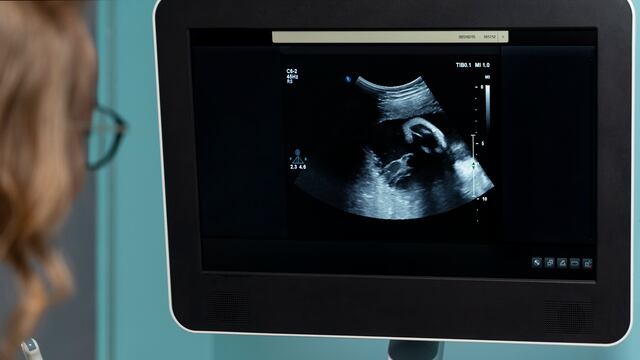

Pues ingresó con una infección grave, por lo que se le realizó una tomografía para descubrir más de su afección.

Cuál fue la sorpresa de los médicos al darse cuenta que la infección de la anciana era provocada por un feto calcificado, una condición denominada como litopedia.

Se trata de un óvulo que se fertiliza fuera del útero que deriva en la muerte del feto y, posteriormente este se calcifica.

Por lo que se decidió realizar una operación para extirpar el feto calcificado que, de acuerdo al equipo médico, estaba ahí desde hace más de 30 años.